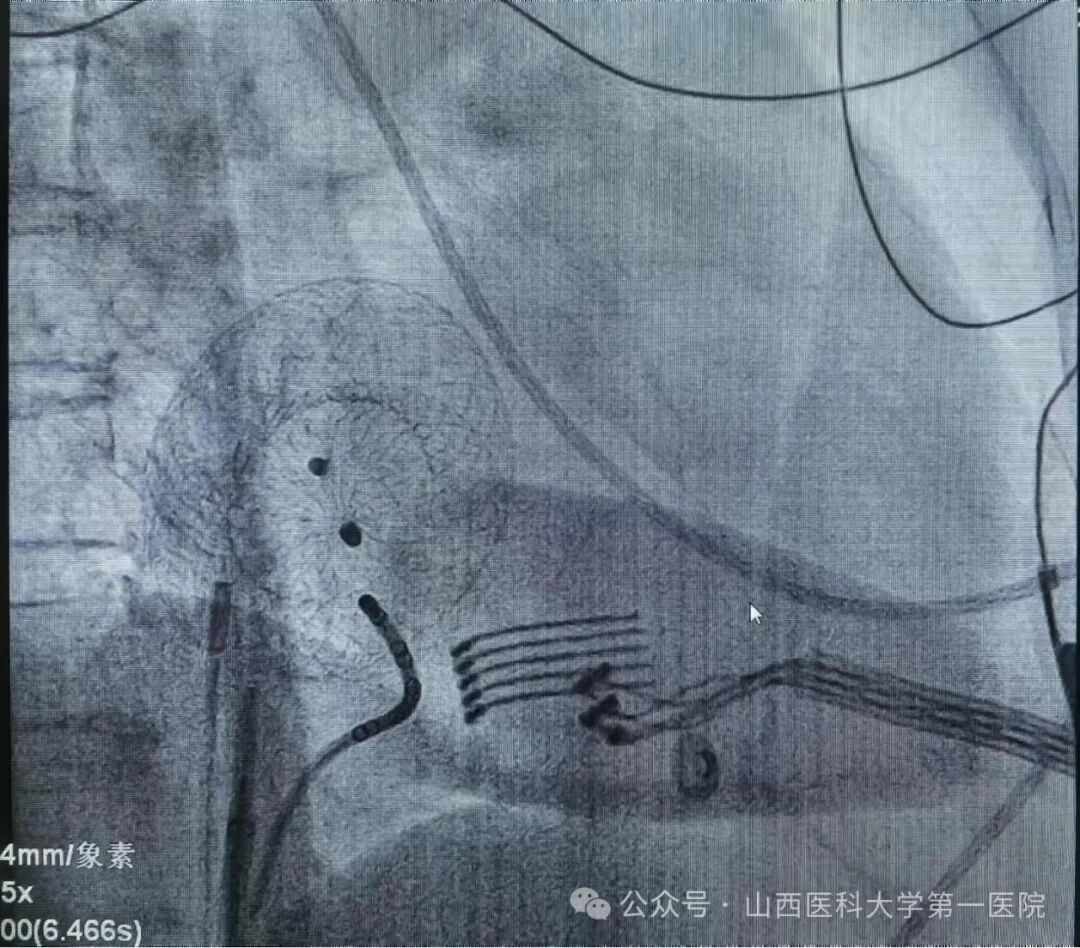

患者术中影像图

双心房标测证实局灶靶点,经消融成功终止房扑